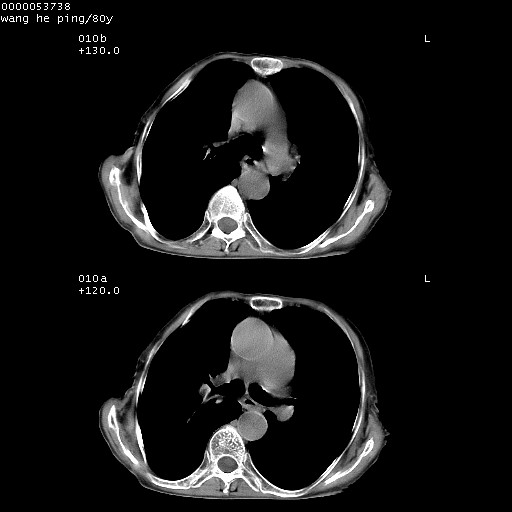

以下是引用黑白光影在2008-8-28 22:33:00的发言:[br]右肺中央型肺癌伴阻塞性肺炎,肺癌肺转移。

以下是引用lshx在2008-8-28 22:06:00的发言:[br]1.右肺中心型肺癌伴阻塞性肺炎,不除外双 肺早期转移。[br]2.心包积液。

以下是引用随光逐影在2008-8-29 7:40:00的发言:[br]1)右肺中心型肺癌伴阻塞性肺炎,肺内转移。2)心包积液(少量)。

以下是引用wqs571018在2008-8-28 21:56:00的发言:[br]右肺中心型肺癌伴阻塞性肺炎可能。

以下是引用liuyue在2008-8-28 22:46:00的发言:[br]1.右肺中心型肺癌伴阻塞性肺炎。[br]2.心包积液(少量)。